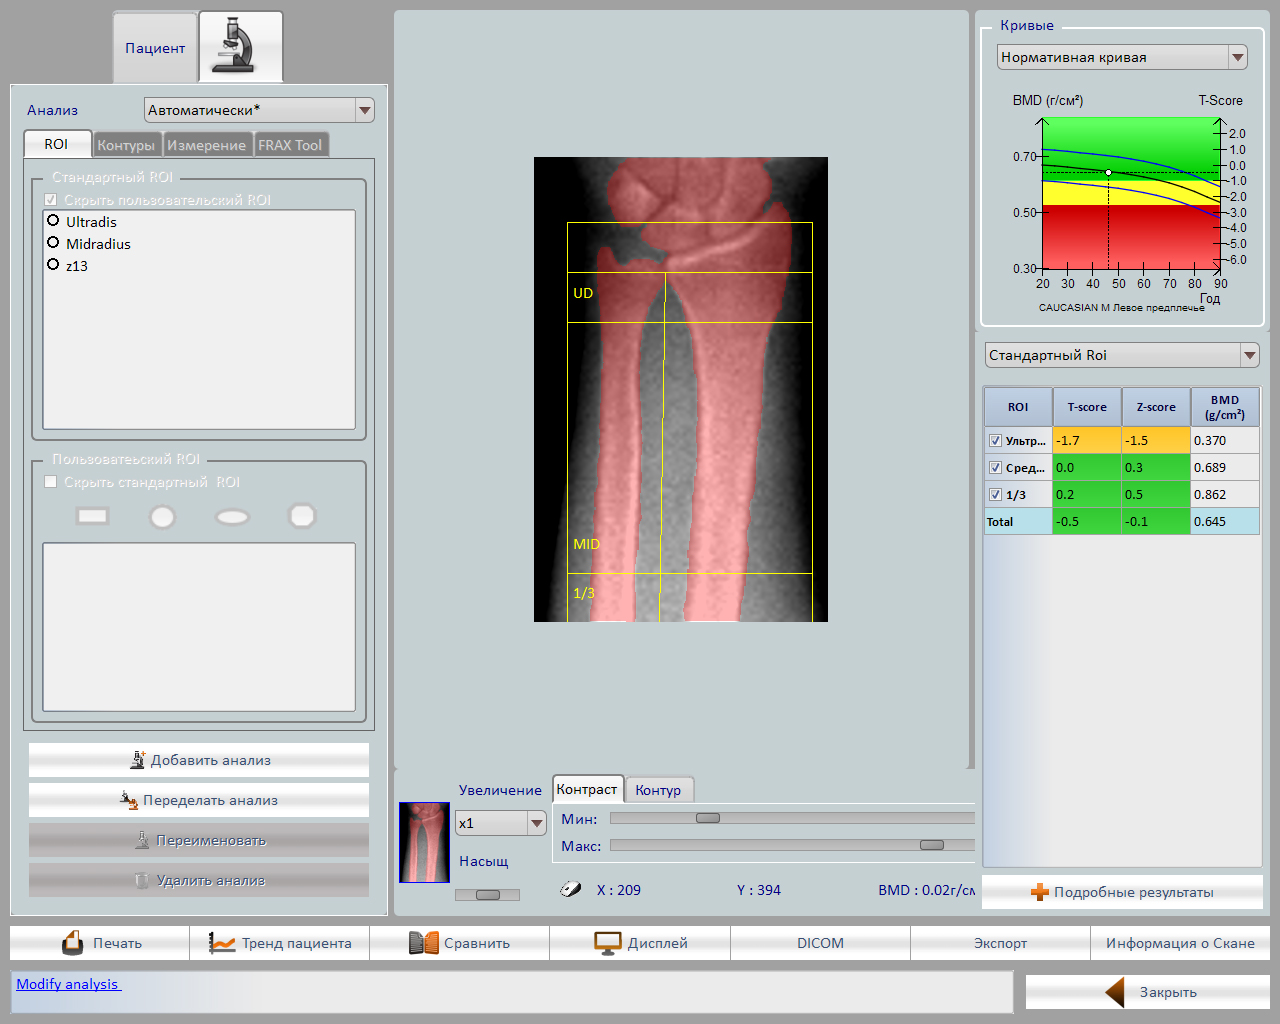

Главной особенностью аппарата является широкий спектр возможных исследований: поясничный отдел позвоночника, проксимальный отдел бедренной кости, кость предплечья, обследование позвоночника в боковой проекции, боковая проекция оценки позвонков, возможность проводить исследования состава тела.

- Автоматический расчет: плотности шейки бедра, вертела бедра, позвоночника, предплечья и треугольника Вордса

- Автоматический и ручной выбор: области интереса (ROI)